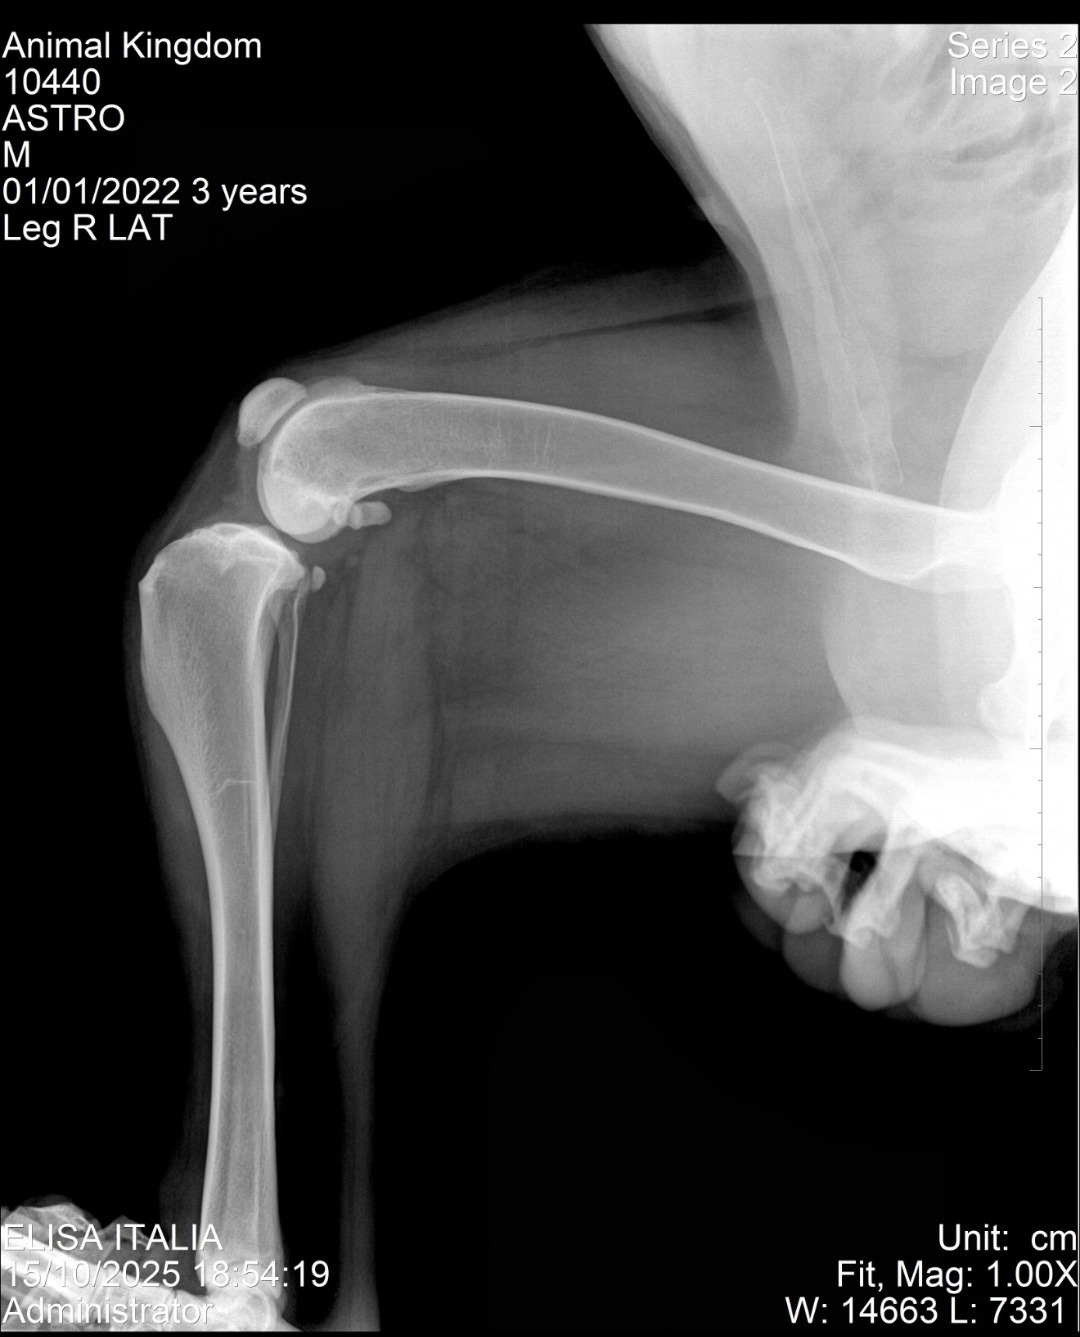

Astro es un perrito gigante y anciano que vive en nuestro refugio. Toda su vida ha ayudado en la rehabilitación de más perritos. Hace tres semanas sufrió la ruptura de un ligamento cruzado, y cuando se preparaba para su cirugía, los exámenes preoperatorios revelaron algo inesperado: una masa en su abdomen.

La operación tuvo que cancelarse, y tras nuevos estudios descubrimos que se trataba de un absceso interno. Astro tuvo que someterse primero a la cirugía de rodilla y luego a otra intervención para retirar la masa. Lamentablemente, durante su recuperación, el otro ligamento también se rompió, ya que todo su peso recaía sobre una sola pata.